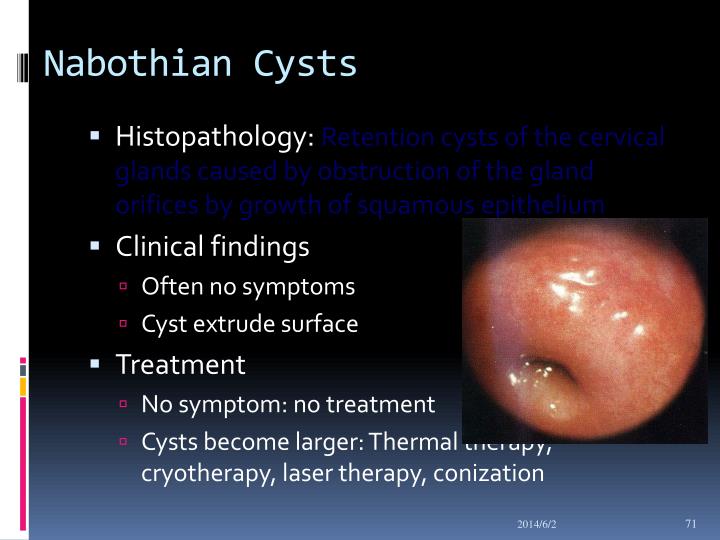

Atualizado: 16 janeiro 2017. Os cistos de Naboth, ou quistos de Naboth, consistem numa desordem uterina, caracterizada pela formação de um ou mais nódulos na parede uterina. As glândulas mucosas no colo uterino ficam cheias de secreção devido ao bloqueio no ducto ou na passagem da glândula. Quando as secreções se acumulam, forma-se um.. Revisão médica: Dr. Gonzalo Ramirez Psicólogo e Clínico Geral. Os cistos são pequenas bolsas ou nódulos preenchidos com líquido ou substâncias semi-sólidas ou gasosas, que podem se desenvolver em qualquer local do corpo, sendo mais comuns na mama, na tireoide, nos ovários ou no fígado. Os cistos são, na maior parte dos casos.

Médico. Usualmente, não é necessário tratamento para o cisto de Naboth. Em casos muito raros, os cistos podem aumentar muito de tamanho, alterando a forma do útero. Nesta situação, o ginecologista pode remover o cisto com um eletrocautério ou bisturi, procedimento que pode ser realizado ambulatorialmente. Referências bibliográficas.. Entenda o que é cisto de Naboth, sintomas, diagnóstico, causas e tratamento. O cisto de Naboth é um tipo de cisto que pode surgir na superfície do colo do útero e causar sintomas como desconforto na região íntima, dor durante as relações sexuais e corrimento vaginal em algumas mulheres. Entenda o que é cisto de Naboth, sintomas.